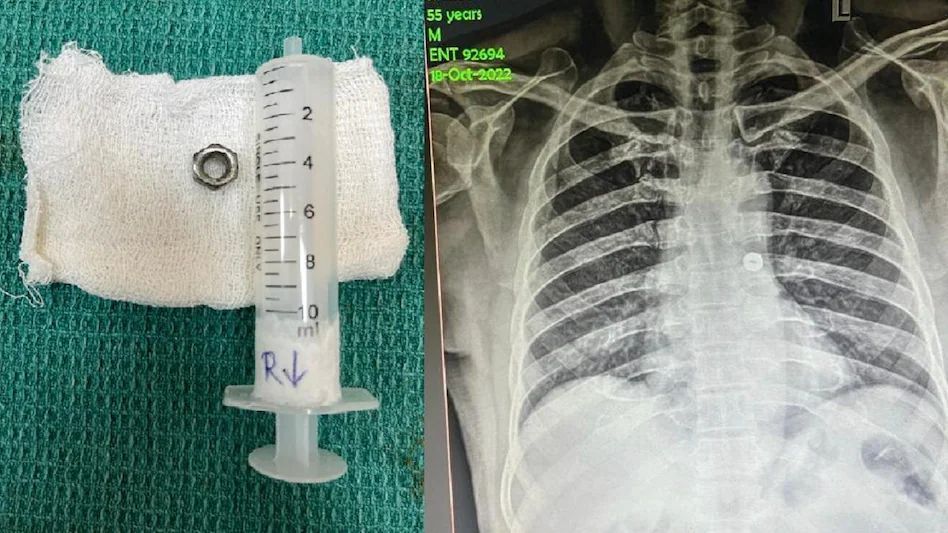

Tamil Nadu News: एक्स-रे में डॉक्टरों ने देखा कि नट शमशुद्दीन की सांस नली में अटका हुआ था और उसके बाएं फेफड़े की ओर जा रहा था। इसके बाद डॉक्टरों ने ऑपरेशन किया और नट निकाल लिया।

ये घटना है तमिलनाडु में कोयंबटूर की है। शमशुद्दीन नाम का शख्स इलेक्ट्रिशियन का काम करता था। 18 अक्टूबर को काम करते हुए उसने गलती से एक लोहे का नट निगल लिया। बताया जाता है कि उसने उसे खांसकर बाहर निकालने की कोशिश की, लेकिन ये संभव नहीं हुआ। आनन फानन में उसे सरकारी अस्पताल में भर्ती कराया गया।

डाक्टरों ने उसका एक्स-रे किया। उसमें डॉक्टरों ने देखा कि नट उसकी सांस नली में अटका हुआ था और उसके बाएं फेफड़े की ओर जा रहा था। बिना समय व्यर्थ किए डाक्टरों ने शमशुद्दीन का ऑपरेशन किया और नट को सफलतापूर्वक निकाल दिया।